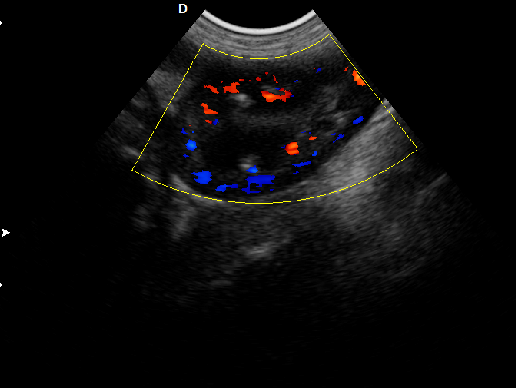

P5-VET手提式獸用彩超機心臟超聲檢查圖

心臟超聲檢查:

心臟超聲是唯一能動態顯示心腔內結構、心臟的搏動和血液流動的儀器,對人體沒有任何損傷。心臟的各個結構清晰地顯示在屏幕上。通過彩超的測量,醫生可了解瓣膜病變的程度以決定保守治療還是手術治療。心肌的增厚、心腔的擴大都要依賴彩超來判斷;對冠心病,彩超能直觀顯示心肌的運動狀況及心功能,向臨床醫生提示心肌缺血的部位。